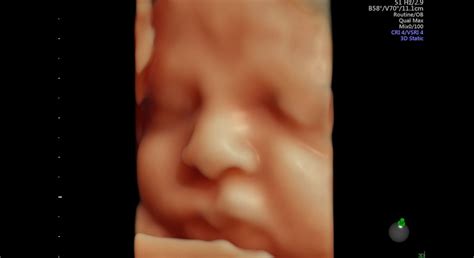

Počas vyšetrenia lekár kontroluje plod kompletne od hlavy až po päty v súlade s medzinárodnými štandardmi. Nad rámec štandardných povinných vyšetrení sa často venuje detailnému posúdeniu srdca plodu, pričom moderné 3D/4D ultrazvukové prístroje umožňujú využiť ich plný potenciál. Pri vyšetrení srdca sa používajú pokročilé techniky ako farebné mapovanie, pulzný Doppler, tkanivový Doppler či STIC 4D zobrazenie srdca, ktoré poskytujú cenné informácie o morfológii a funkcii srdca plodu.

Okrem toho, na rozdiel od bežných 2D morfologických vyšetrení, sa pri každom plode realizuje aj 3D vyšetrenie mozgu s využitím tomografického ultrazvukového zobrazenia. Táto metóda umožňuje zobraziť mozog plodu v 0,5 mm rezoch v troch na seba kolmých rovinách, podobne ako pri magnetickej rezonancii alebo CT, avšak ide o neinvazívne ultrasonografické vyšetrenie.